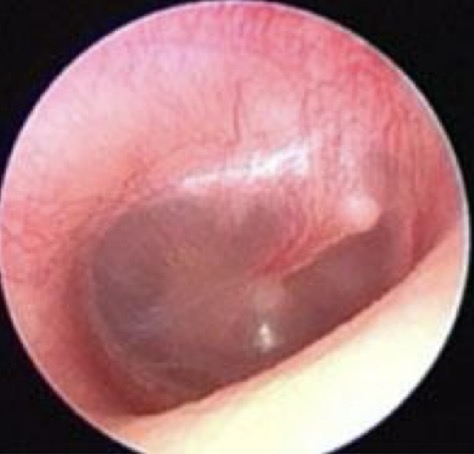

Comment on this tympanic membrane

Healthy tympanic membrane

Can see handle of malleus

Can see cone of light

Translucent

No build up of fluid